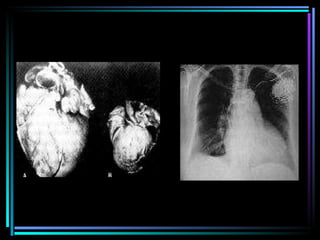

Radiografia mostrando o aumento do volume do coração chagásico (cardiomegalia)

Cardiopatia chagásica crônica. Nota-se importante cardiomegalia e a presença de lesão vorticilar (aneurisma da ponta do ventrículo esquerdo

Radiografia mostrando oaumento do volume do coração chagásico (cardiomegalia)

Cardiopatia chagásica crônica.Nota-se importante cardiomegalia e a presença de lesão vorticilar (aneurisma da ponta do ventrículo esquerdo